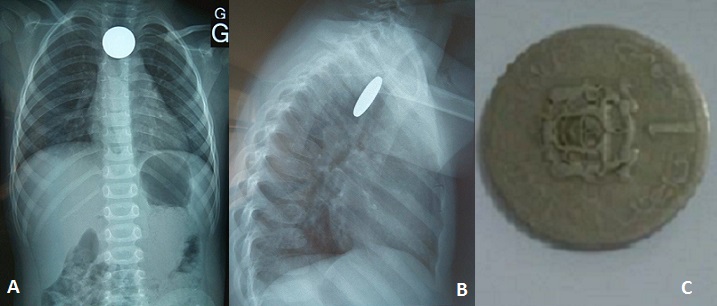

Ingestion accidentelle d’une pièce de monnaie en intra-oesophagien

Il s'agit d'une jeune fille de 3 ans, sans antécédent particulier, admise aux urgences du CHU Mohammed VI d'Oujda dans un tableau de dysphagie aux solides avec hyper-sialorrhée, l'interrogatoire a trouve la notion d'ingestion accidentelle d'une énorme pièce de monnaie enclavée à l'entrée de l'oesophage. La réalisation d'une radiographie thoracique de face a montré la présence d'un énorme objet radio-opaque se projetant au niveau de la région cervicale, le cliché de profil confirmé la position postérieure du CE œsophagien par rapport aux clartés antérieures du larynx, de la trachée et de la carène. L'extraction a été faite au bloc opératoire par l'utilisation d'une endoscopie oesophagienne. Les suites ont été simples. Les ingestions de corps étrangers (CE) surviennent, Le plus souvent d'une façon accidentelle, dans la majorité des cas avant l'âge de 5 ans. Les symptômes liés à l'ingestion d'un CE dépendent de l'âge de l'enfant, de ses antécédents (chirurgie digestive), de la taille et de la localisation du CE et/ou de la survenue d'une complication éventuelle (ulcération, perforation digestive...). Si la plupart des CE ingérés traversent le tractus digestif sans manifestation clinique ni complication, 10 à 20% d'entre eux doivent être extraits par voie endoscopique en urgence et moins de 1% nécessite un traitement chirurgical en raison d'une complication majeure: soit une obstruction oesophagienne, ou une perforation pouvant être responsable d'une médiastinite.